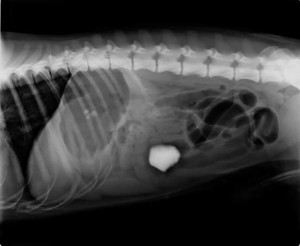

radio cochon d'inde

Radiographie d’une cochon d’inde en gestation réalisée par le Dr Reboli et Charlotte